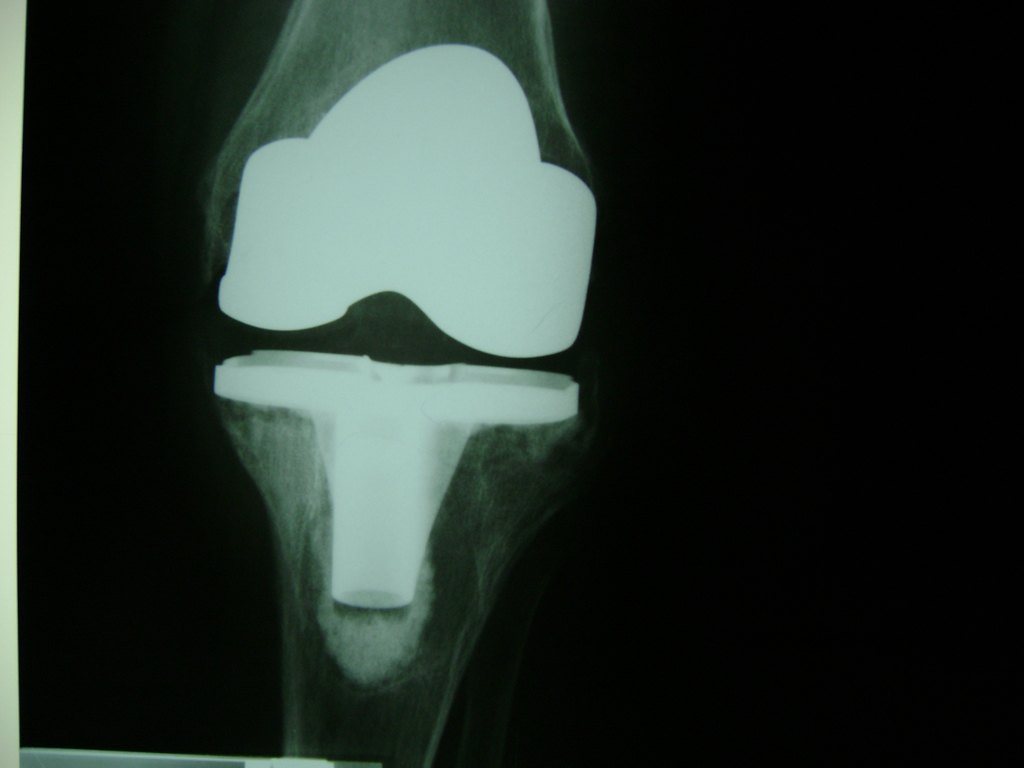

Cirugías de Húmero - Rodilla